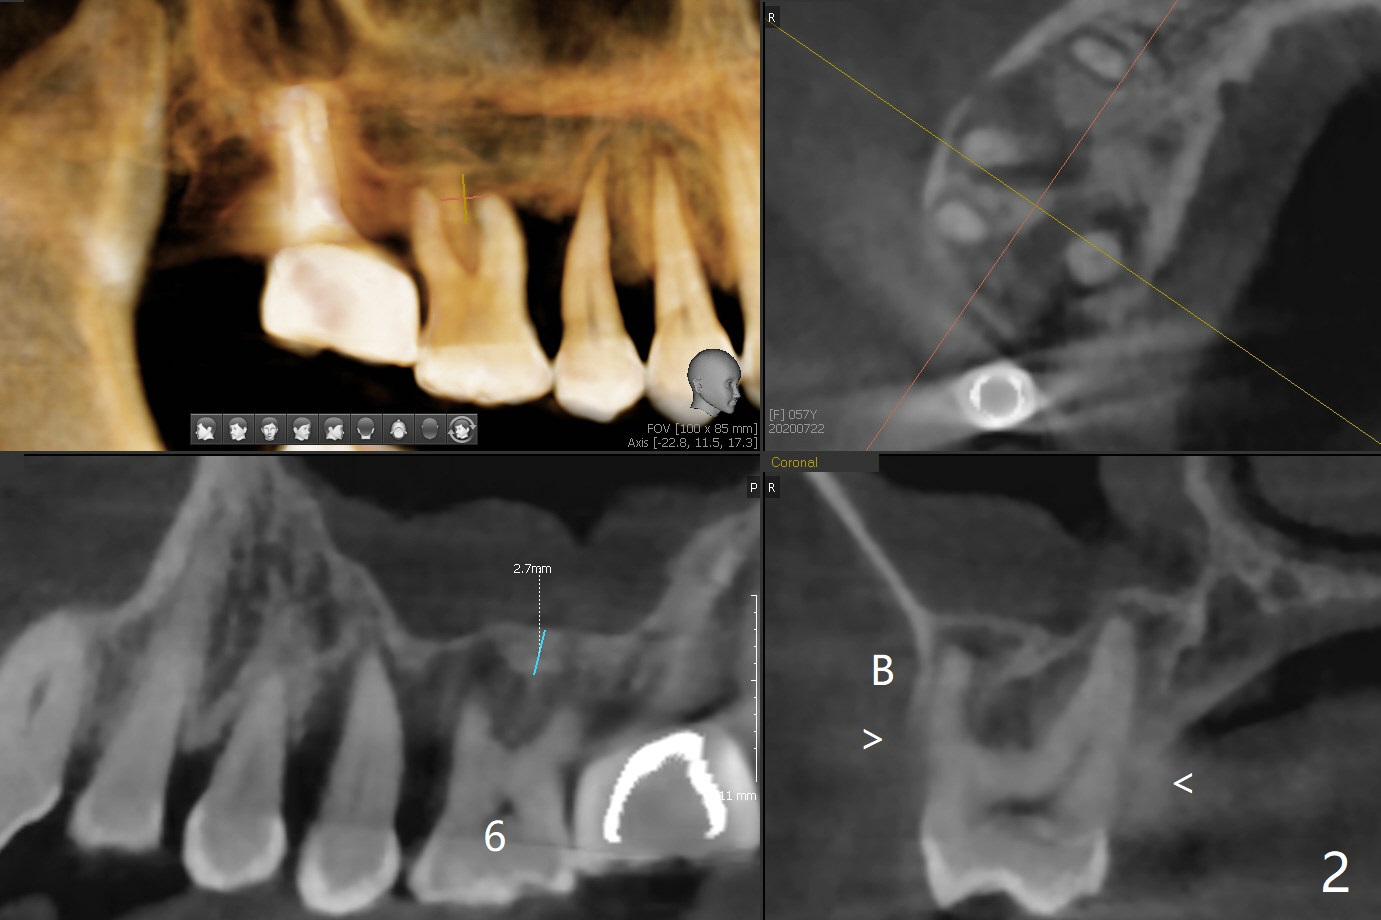

57岁女严重牙周炎,主诉右上磨牙食物堵塞(图一:圆圈)。第一磨牙骨质吸收,松动,需要拔除,尽管骨壁2-3毫米(图二),使用导航应该能取得5乘7.3毫米植体(图三绿色)初步稳定性。上颌窦膜厚,提升术不容易破裂,使用PRF膜预防及修补。由于近中骨质缺损严重(图三 *),植体可以再提高些(箭头),利用粘性骨做提升以及骨质缺损充填,似乎颊侧骨质多些(图五),植体可以小些,万一不行,就做提升和植骨。左上磨牙区骨壁更薄(图四,约1毫米),外提升术之后再种植。